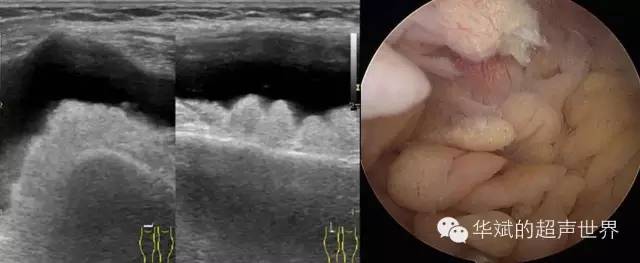

滑膜树枝状脂肪瘤(Synovial lipoma arborescens)好发于膝关节,髌上囊常见。滑膜脂肪瘤病大体上呈灰白灰黄色,滑膜呈淡黄色粗大乳头状突起,边缘光滑。显微镜镜下滑膜呈绒毛状增生;绒毛被覆1-4层滑膜细胞,部分区域滑膜细胞不同程度增生;滑膜下层成熟脂肪细胞呈灶性或弥漫性浸润;绒毛内可见大量扩张充血的毛细血管,部分病例有不同程度的淋巴细胞、浆细胞浸润。对于该病的本质也存在两种观点,一种认为是关节内滑膜来源的真正的良性肿瘤;一种观点认为滑膜脂肪瘤病不是一种真正的肿瘤,而是滑膜的一种类似良性肿瘤的增生性病变。尤其是对关节内软骨长期受损的一种适应性和保护性的滑膜增生。至于滑膜脂肪瘤病确切的病因和发病机制还不清楚,多数学者认为是被灶性或弥漫的成熟脂肪细胞浸润的滑膜呈绒毛状增生的结果。影像学上,可见积液扩张的滑膜囊内有大量的附着于壁上的结节样含脂肪成分突起。声像图上呈现为高回声。(* arborescens译为树枝状并不准确,姑且用之)

图5 髌上囊内的滑膜树枝状脂肪瘤。右图为关节镜下所见。